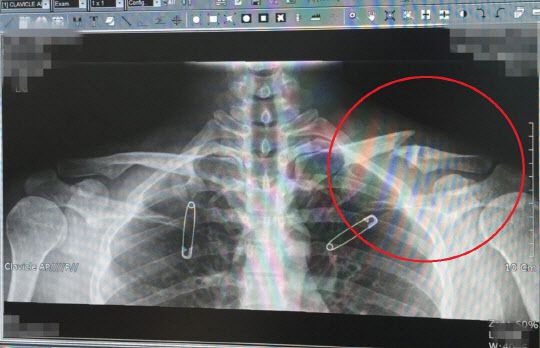

과거 유아인은 2013년 영화 촬영 중 어깨 근육 파열에 이어 2015년 골종양 판정을 받은 것으로 전해졌습니다. 당시 유아인은 병무청으로부터 '현역 자원 활용 불가' 판정을 받으며 면제가 되었습니다.

유아인이 골종양을 앓고 있다는 사실이 알려진 이후 참석한 드라마 제작발표회 현장에서 "오른쪽 어깨에 종양이 있지만 양성이다. 특이 케이스로 사이즈가 비이상 적으로 커져서 관찰을 유심히 하고 있다"고 설명했습니다.

당시 일부 매체들은 유아인이 골종양(골육종) 때문에 병역 면제 판정을 받았다고 보도했는데 일부 누리꾼들은 이에 대해 '골종양'과 '골육종'은 엄연히 다른 질병이라 지적하기도 했습니다.

유아인과 소속사 측은 유아인의 군면제 사유에 대해 '골종양'이라고는 했어도 '악성 골종양', '골육종'이라고 언급한 바는 없었지만 유아인이 골육종 때문에 병역 면제를 받았다는 일부 보도 때문에 유아인은 암환자가 되기도 했습니다.

유아인의 군면제 사유는 악성이 아닌 양성 골종양으로 양성 골종양은 종류도 많고 발생하는 부위도 다양합니다. 또 그 예후의 차이가 크기 때문에 완치를 장담할 수 없는 편으로 알려져 있습니다.